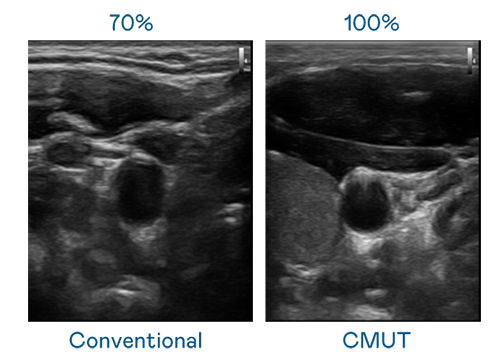

CMUT 技术是一种用电容式微机电元件来产生超音波讯号的技术。与传统 PZT 压电式技术相比,CMUT 频宽增加 30%,更宽频的超音波讯号让影像解析度大幅提升,是实现高影像品质医疗超音波扫描、促进精准医疗发展的关键技术。

大频宽带来超清晰影像

超音波影像的解析度高低,首先取决于探头能发出的讯号频宽。DB真人旗舰 CMUT 可提供高清晰的超音波讯号,提供高频宽、高灵敏度、影像纹理细节更高的超音波影像,协助医护人员缩短影像判读时间及利用精准的医疗影像进行诊断。